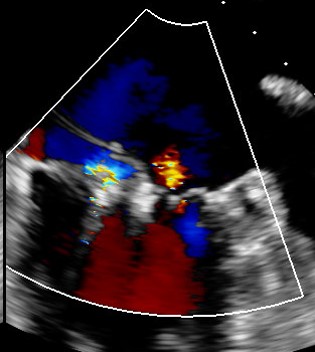

Before: TEE image of posterior leaflet flail and severe MR

After: TEE image of posterior leaflet flail with trace MR following procedure